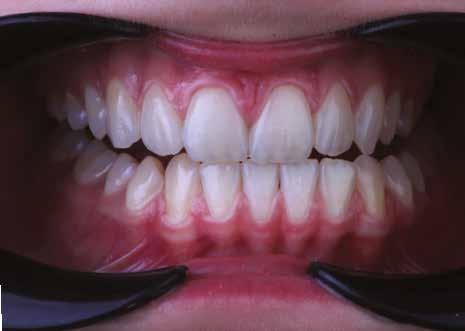

A fogászati kezelések során manapság már nem kizárólag az esztétikai megjelenés helyreállítására törekszünk. Sokszor a kedvezőtlen esztétikai megjelenés hátterében álló okok következményes módon a fogazat funkcionális működését is károsítják, így a kezelések során ezeknek a helyreállításával is foglalkoznunk kell. A különböző funkcionális és esztétikai diszkrepanciák kezelésére számtalan módszer létezik, ám ezen fogászati beavatkozások mindegyikében közös, hogy a kivitelezésük során nagyon szoros együttműködésre van szükség a kezelést végző fogorvos és a munkáját segítő fogtechnikus között. Az alábbi esetbemutatás során egy fiatal hölgypáciens fogazatának héjak alkalmazásával történő esztétikai és funkcionális rehabilitációját szeretnénk ismertetni.

Esetbemutatás

A 19 éves hölgypáciens azzal a kéréssel jelentkezett a rendelőnkbe, hogy szebb fogakat szeretne. Az első konzultáció alkalmával megkérdeztük, hogy mi zavarja leginkább a fogazatának jelenlegi megjelenésében, valamint azt is megbeszéltük vele, hogy milyen végeredmény elérése esetén lenne maradéktalanul elégedett. Ebben az esetben a kezelési célokat az alábbiakban határoztuk meg:

A páciens fogazata esztétikai megjelenésének és funkcionális működésének a lehető legtöbb, saját foganyag megtartása mellett történő helyreállítása (1. és 3. ábra). A lehető legideálisabb esztétikai végeredmény elérése érdekében néhány esetben a fogak alakjának módosítá -

sára is szükség van (2. és 4. ábra).

A kezelés megtervezése során kifejezett jelentősége van annak, hogy jó kommunikáció legyen a páciens, a fogorvos és a fogtechnikus között. A páciens leendő fogazatának természetes megjelenését a kezelésben részt vevő team szakmai felkészültsége, gyakorlati tapasztalata és a kezelés sikerességének irányába történő elkötelezettsége biztosítja. A beavatkozások megkezdése előtt megtörtént a páciens anamnézisének a felvétele, valamint a klinikai kivizsgálását is elvégeztük. Ezt követően lenyomatokat készítettünk a kiindulási állapotról, majd a kiindulási helyzetet extra- és intraorális fotók segítségével is rögzítettük (13. a-c. ábra).